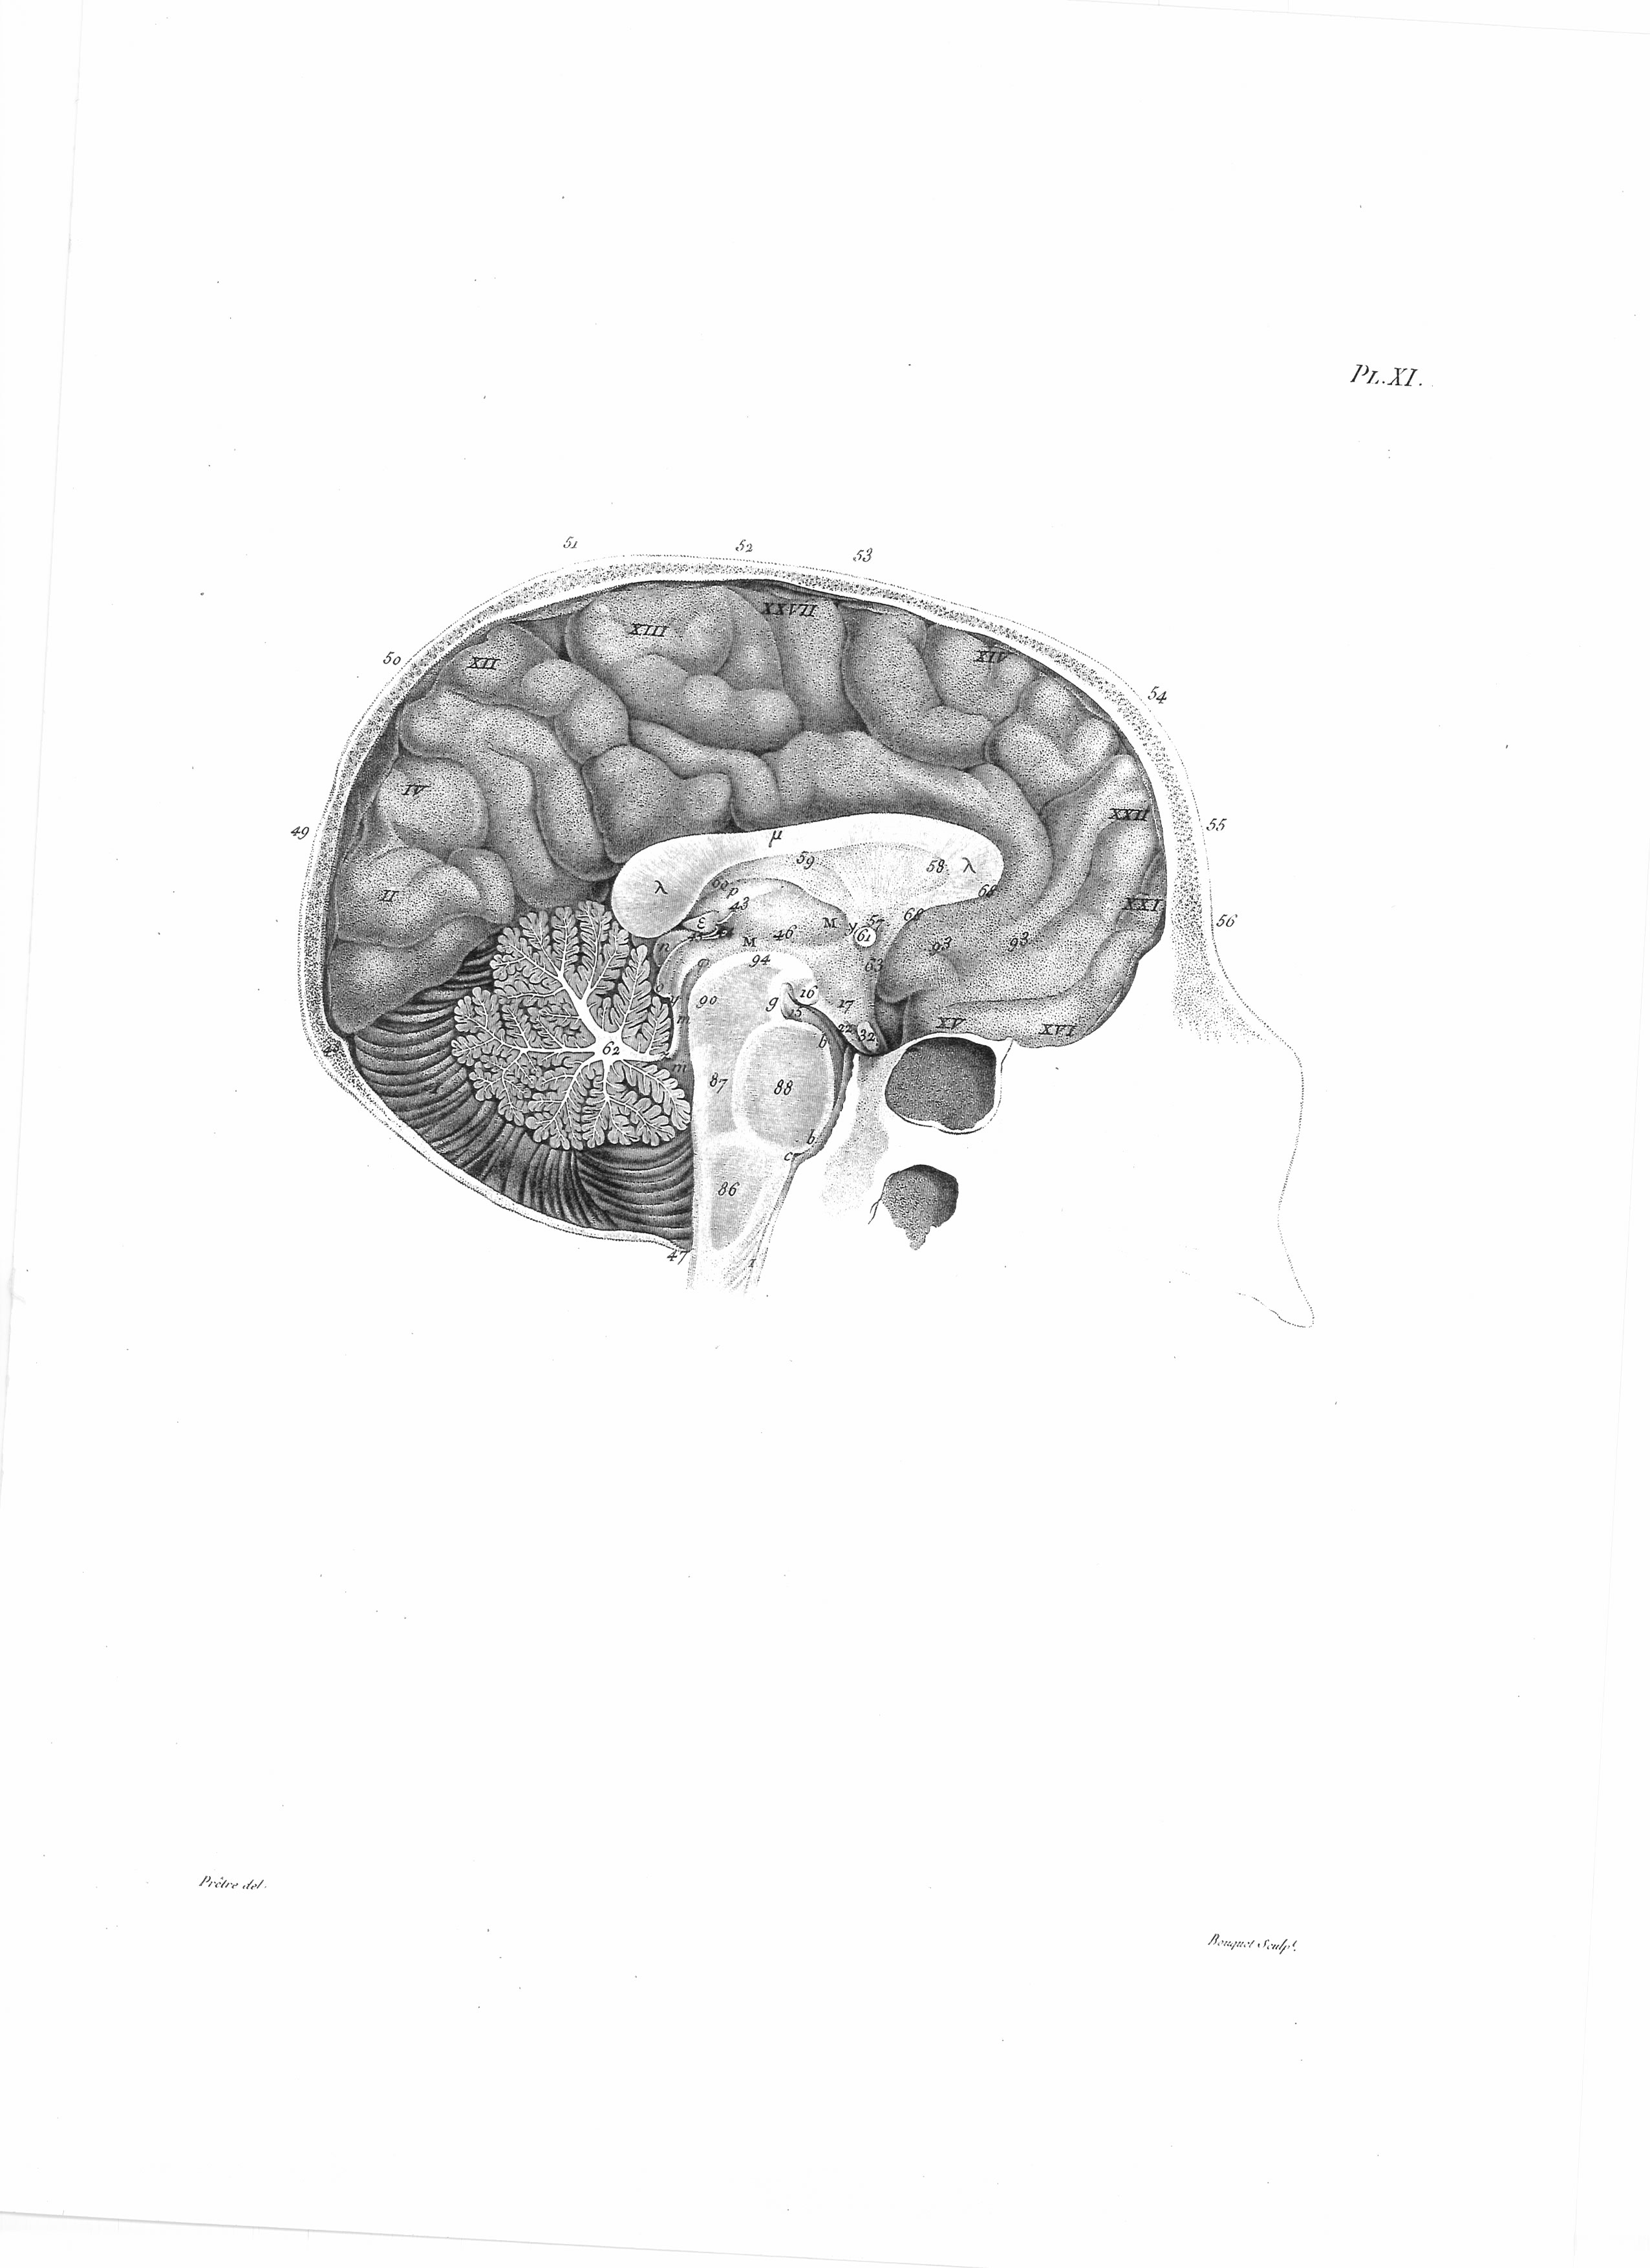

Gall, F. J. (1818). Anatomie et physiologie du système nerveux en général, et du cerveau en particulier, Avec des observations sur la possibilité de reconnoître plusieurs dispositions intellectuelles et morales de l´homme et des animaux, par la configuration de leurs têtes.

Librairie Grecque-Latine-Allemande, Vol. 3, I-XXXV u. 1-379 100 planches.